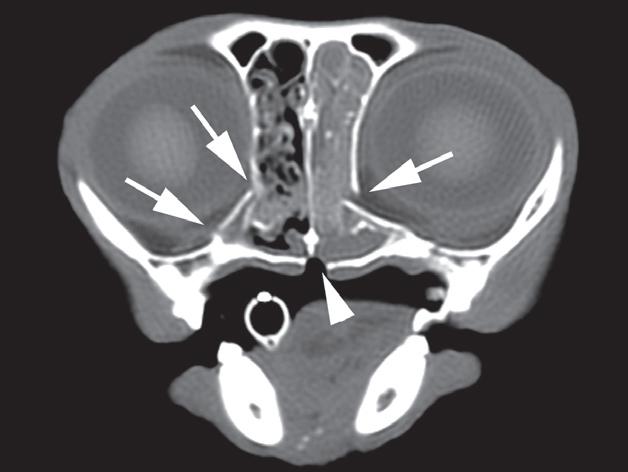

Rycina 1.4.5. Zapalenie mięśni żwaczy (pies) TK

Badanie wykonano u 1,5-rocznego, kastrowanego rottweilera z szybko postępującym brakiem możliwości otwierania pyska. Prezentowane obrazy TK wykonano bezpośrednio po podaniu środka kontrastowego. Widoczne jest umiarkowane, rozlane wzmocnienie pokontrastowe mięśni żwacza i skroniowego po lewej stronie (a, b – strzałki).

Wydaje się, że mięśnie skrzydłowe są niezmienione (a, b – grot strzałki).

Biopsja mięśni ujawniła rozlane, przewlekłe, limfoplazmocytarne zapalenie mięśni z zanikiem i włóknieniem